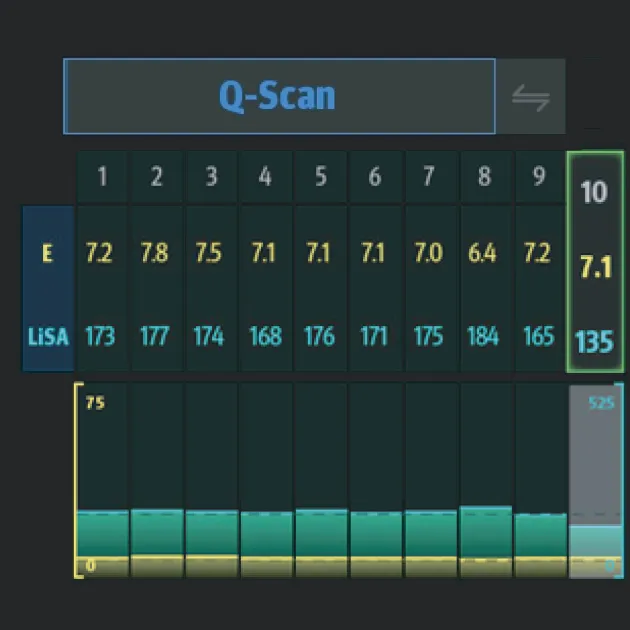

Быстрое интеллектуальное получение данных Q-сканирования

- Нажатием одной кнопки можно автоматически и непрерывно получать 10 групп эффективных данных и проводить интеллектуальный анализ

- Точные и достоверные результаты обнаружения могут быть получены немедленно, всего через 7 секунд после позиционирования